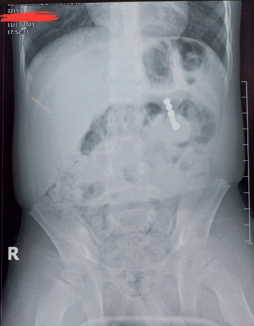

Chiều

ngày 13/11/2023 bệnh nhi B.N.H 4T được gia đình cho đến Bệnh viện Trẻ em Hải

Phòng khám vì ho, sốt. Trong quá trình thăm khám và làm xét nghiệm, các bác sĩ

tình cờ phát hiện một chuỗi dị vật cản quang dạng cầu nằm trong ổ bụng , ngang

mức dạ dày.

Hình1: Chuỗi dị vật cản quang dược

phát hiện tình cờ qua phim chụp bụng không chuẩn bị